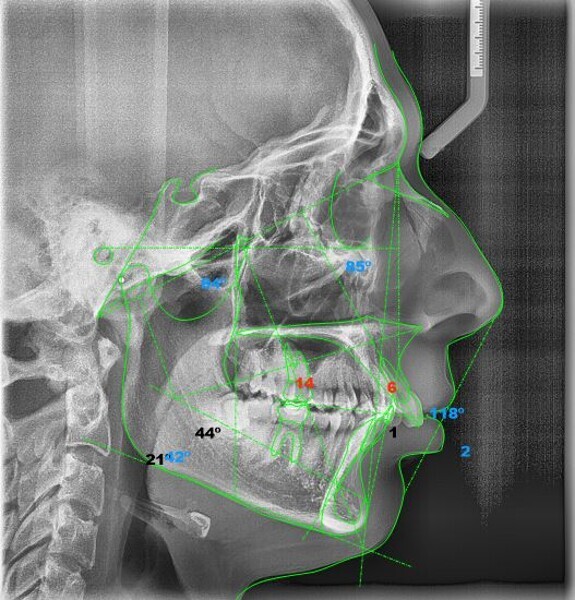

In the radiographic analysis, the dental panoramic tomogram revealed that the two mandibular third molars were unerupted and horizontalised in the mandible. Nothing else relevant was observed in the radiograph (Fig. 3). A cephalometric radiograph was used to perform the cephalometric analysis according to Steiner,6 Ricketts7, 8 and McNamara9 (NemoCeph Studio, Nemotec Fig. 4).

In the Steiner analysis, the SNB angle of 74° suggested mandibular retrusion. Likewise, the ANB angle of 7° indicated Class II, which was also confirmed by Wits analysis (8.3 mm). The results indicated a protrusion of the maxillary incisors and a decreased inter-incisal angle of 118°, which suggested protrusion of the maxillary and mandibular incisors (Fig. 5).

In the Ricketts analysis, a dolichofacial pattern, that is, a facial axis of 84°, was diagnosed. The analysis also confirmed the protrusion of the incisors (Fig. 6).

The McNamara analysis revealed that the size of the mandible that would correspond to the dimensions of the maxilla (91.0 mm) would be between 114.0 mm and 117.0 mm and not the current size of 111.9 mm,9 indicating that the mandible was smaller than it should have been. However, the maxillomandibular difference was 20.9 mm, indicating a Class II skeletal pattern (Fig. 7). From the aforementioned information, we determined a Class II skeletal pattern and dental relationship with retrusion of the lower jaw and an increased overjet and overbite.